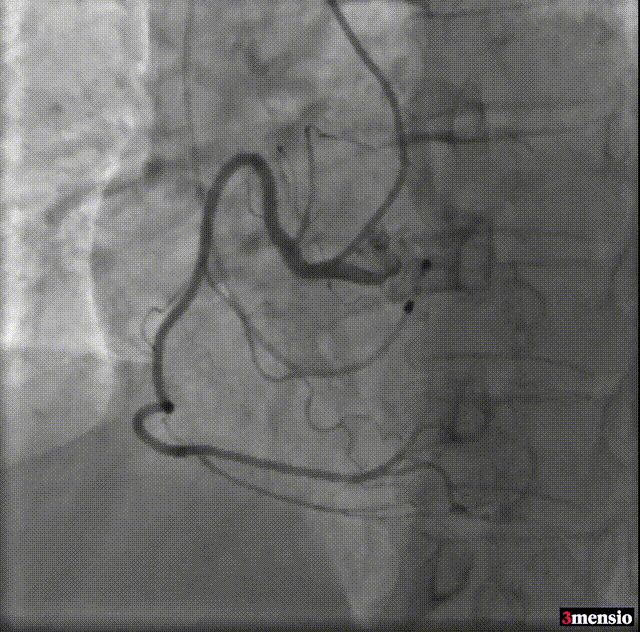

手术影像

术前冠脉造影

主动脉根部造影